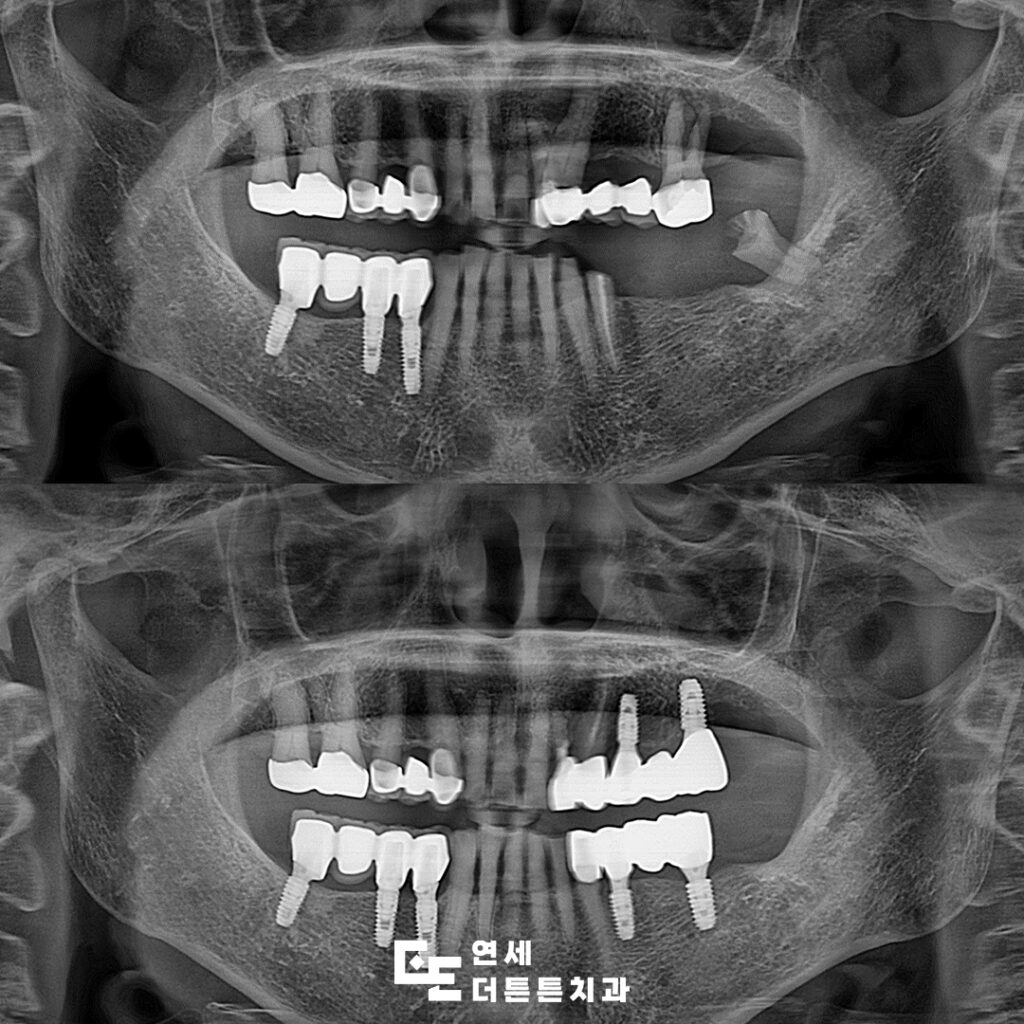

오늘은 망가진 어금니 기능 회복을 위해 임플란트를 진행하신 환자분을 소개해 드리도록 하겠습니다.

환자분께서는 왼쪽 아래 어금니가 다 빠져버리고 오른쪽으로만 식사를 하시다보니 불편하여 치료 상담을 위해 도봉동치과에 내원해 주셨는데요. 왼쪽 위에는 오래된 브릿지가 있었고 아래쪽은 상실한지 오래 되어 기능을 못하고 있는 상태로 위쪽의 브릿지를 제거하고 위, 아래 임플란트를 진행하시기로 계획을 수립하였습니다.